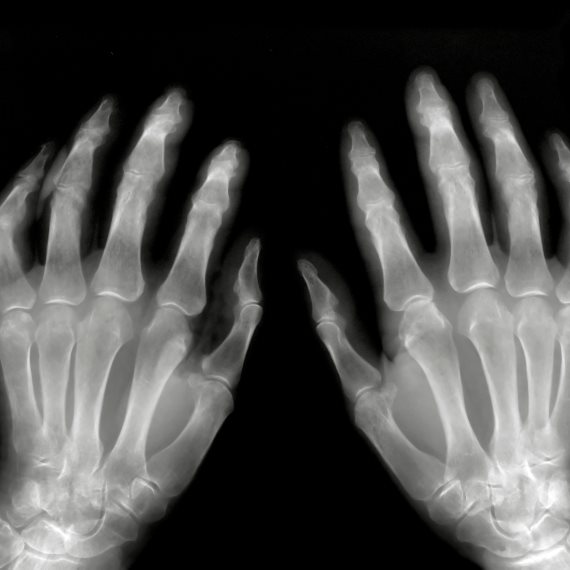

צילום אילוסטרציה: Ingram Image